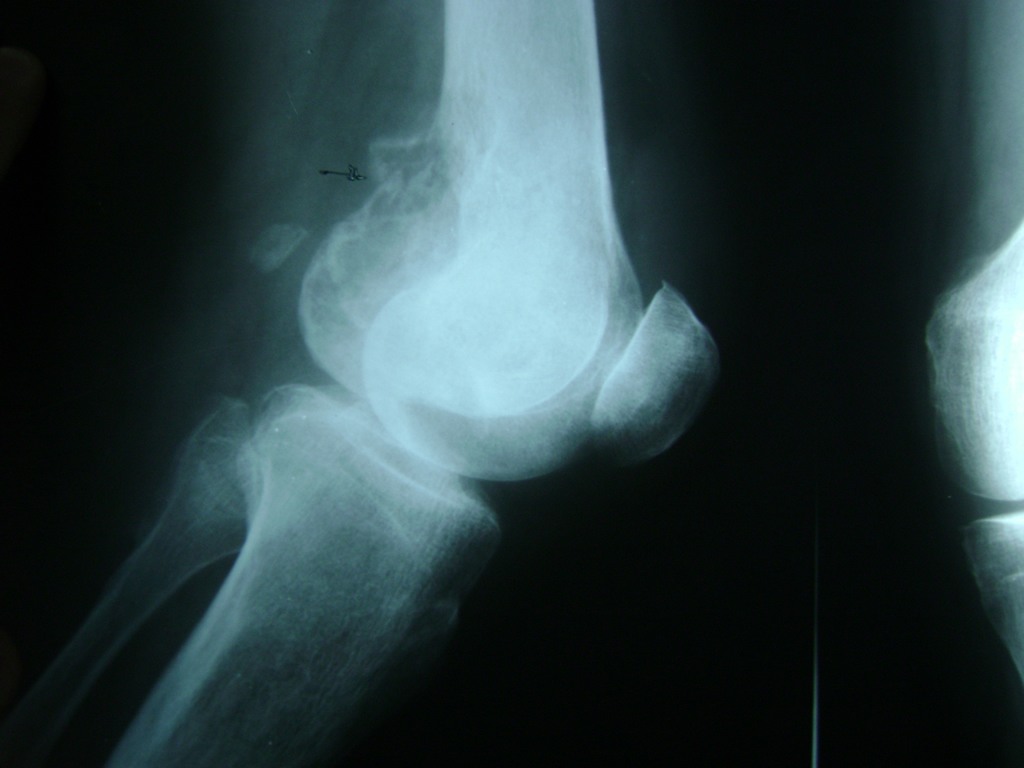

Húmero - Rodilla

La artroscopia de rodilla es un cirugía en el cual la estructura interna de la articulación es examinada ya sea para realizar un diagnostico o para realizar un tratamiento, este procedimiento se realiza utilizando un instrumento parecido a un pequeño tubo llamado artroscopio.